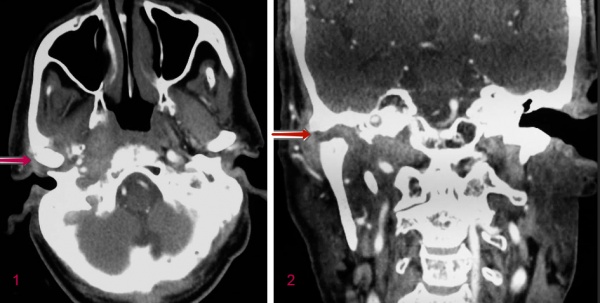

КТ пациента со злокачественным наружным средним отитом. Эрозия височно-нижнечелюстного сустава и помутнение мягких тканей барабанной полости. 1 - осевой, 2 - венечный.

• Методы визуализации. При сцинтиграфии определяются очаги воспаления височной кости и основания черепа. КТ, магнитно-резонансная томография головного мозга, в дополнение к костным изменениям, дают возможность выявлять эпидуральную эмпиему, признаки повреждения матки и обнаруживать абсцессы в центральной нервной системе.